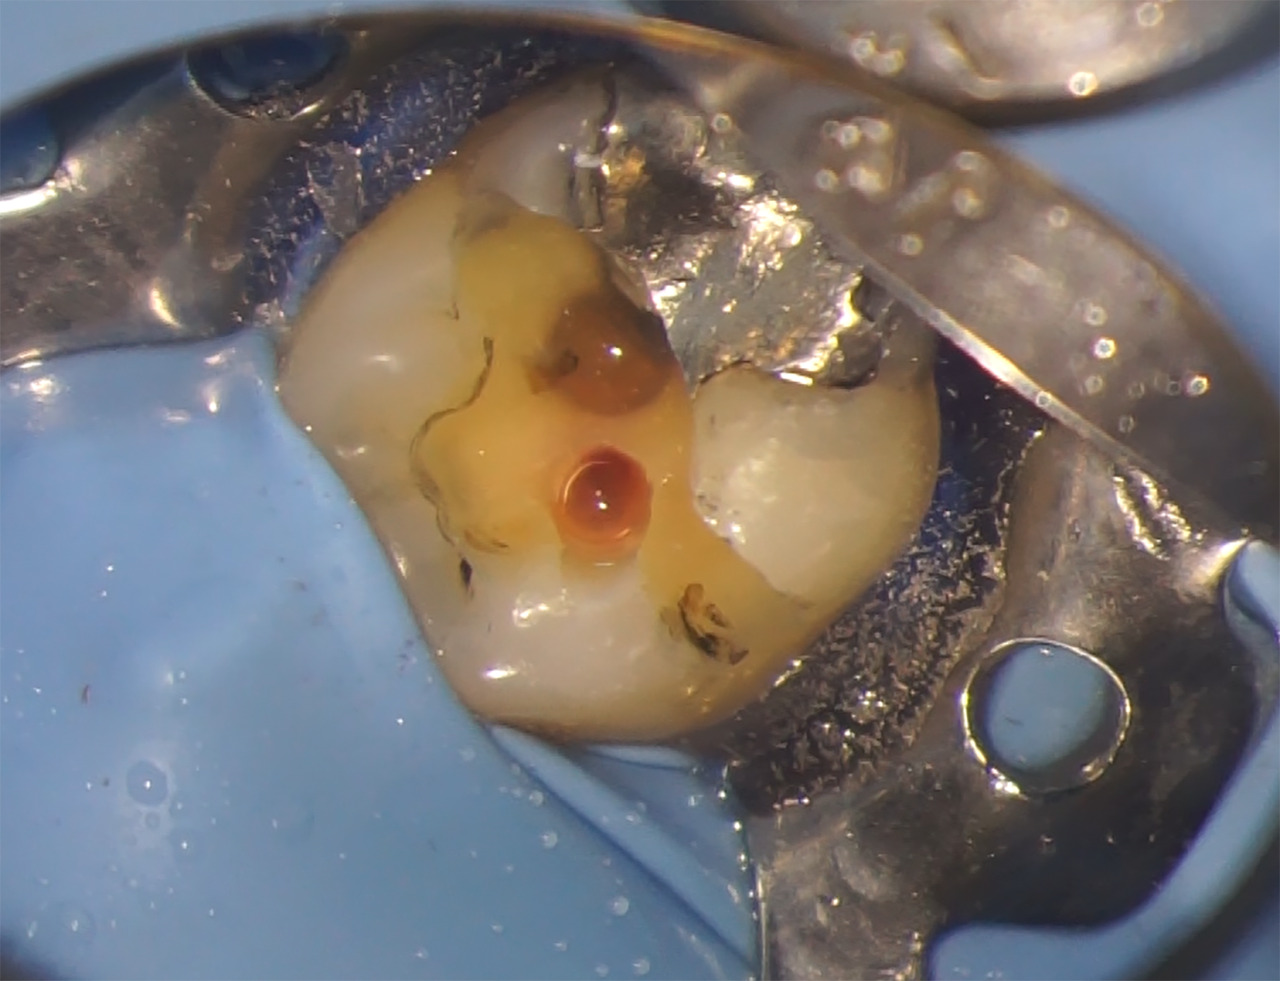

Réalisation de la cavité d’accès

Dans un premier temps, l’obturation à l’amalgame est éliminée en partie avec une fraise transmétal Talon 12 – (Tri Hawk, USA). Le reste de l’obturation sera éliminé lors de la confection de la restauration coronaire. Pour la cavité d’accès, il est décidé de réaliser une cavité de type Ninja qui permet d’accéder directement et uniquement au canal concerné (Fig.6).

Pour ce faire, la corne pulpaire mesio-vestibulaire et sa projection sur la face occlusale de la dent sont repérées sur l’image 3D issue de la segmentation. Cette trajectoire est mémorisée, et sert de guide pour le chemin de la fraise qui va permettre de réaliser une exposition pulpaire directe, franche et de petite taille.

La cavité est réalisée avec une fraise boule diamantée de diamètre 14 (Microcopy- USA) montée sur un contre-angle rouge utilisé avec un spray abondant.

Fig.6 : Vue occlusale de la dent avec la cavité d’accès réalisée.